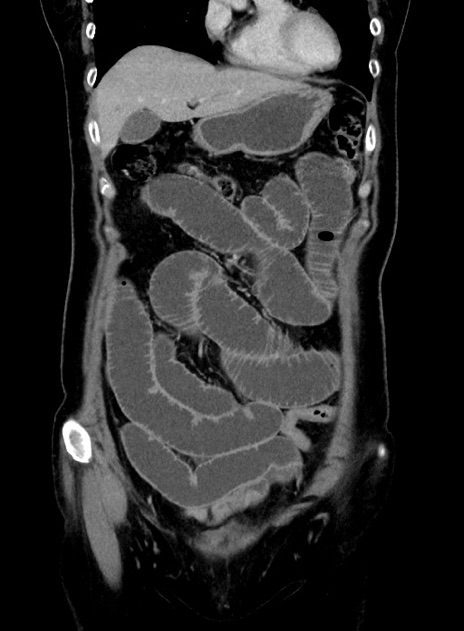

症例9(冠状断像)

【症例】 60歳代女性

【主訴】むかつき、みぞおちの痛み

【現病歴】3日前よりむかつきがあり、食事がとれない。

【既往歴】糖尿病

【身体所見】発熱なし、心窩部圧痛軽度あるも、腹膜刺激症状なし。

【データ】WBC 7400、CRP 1.92